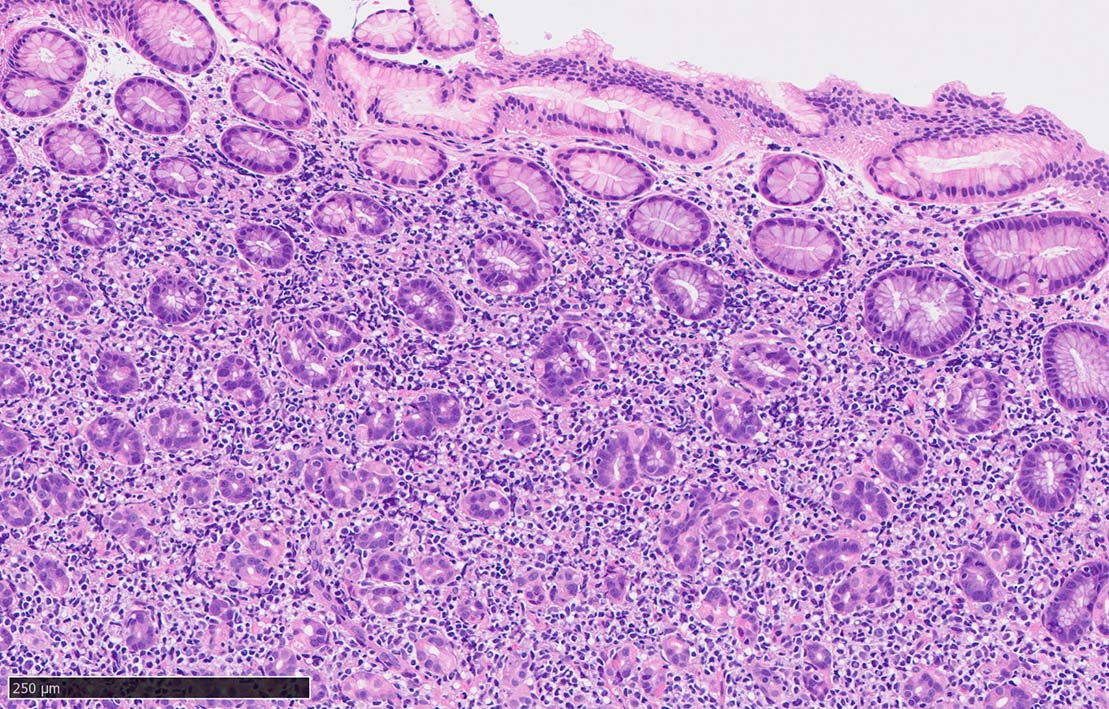

Signet-ring cell lymphoma of the stomach

60 year-old male. 胃生検組織

stomach biopsy, HE

x200

非結節部位

固有腺のLEL様所見